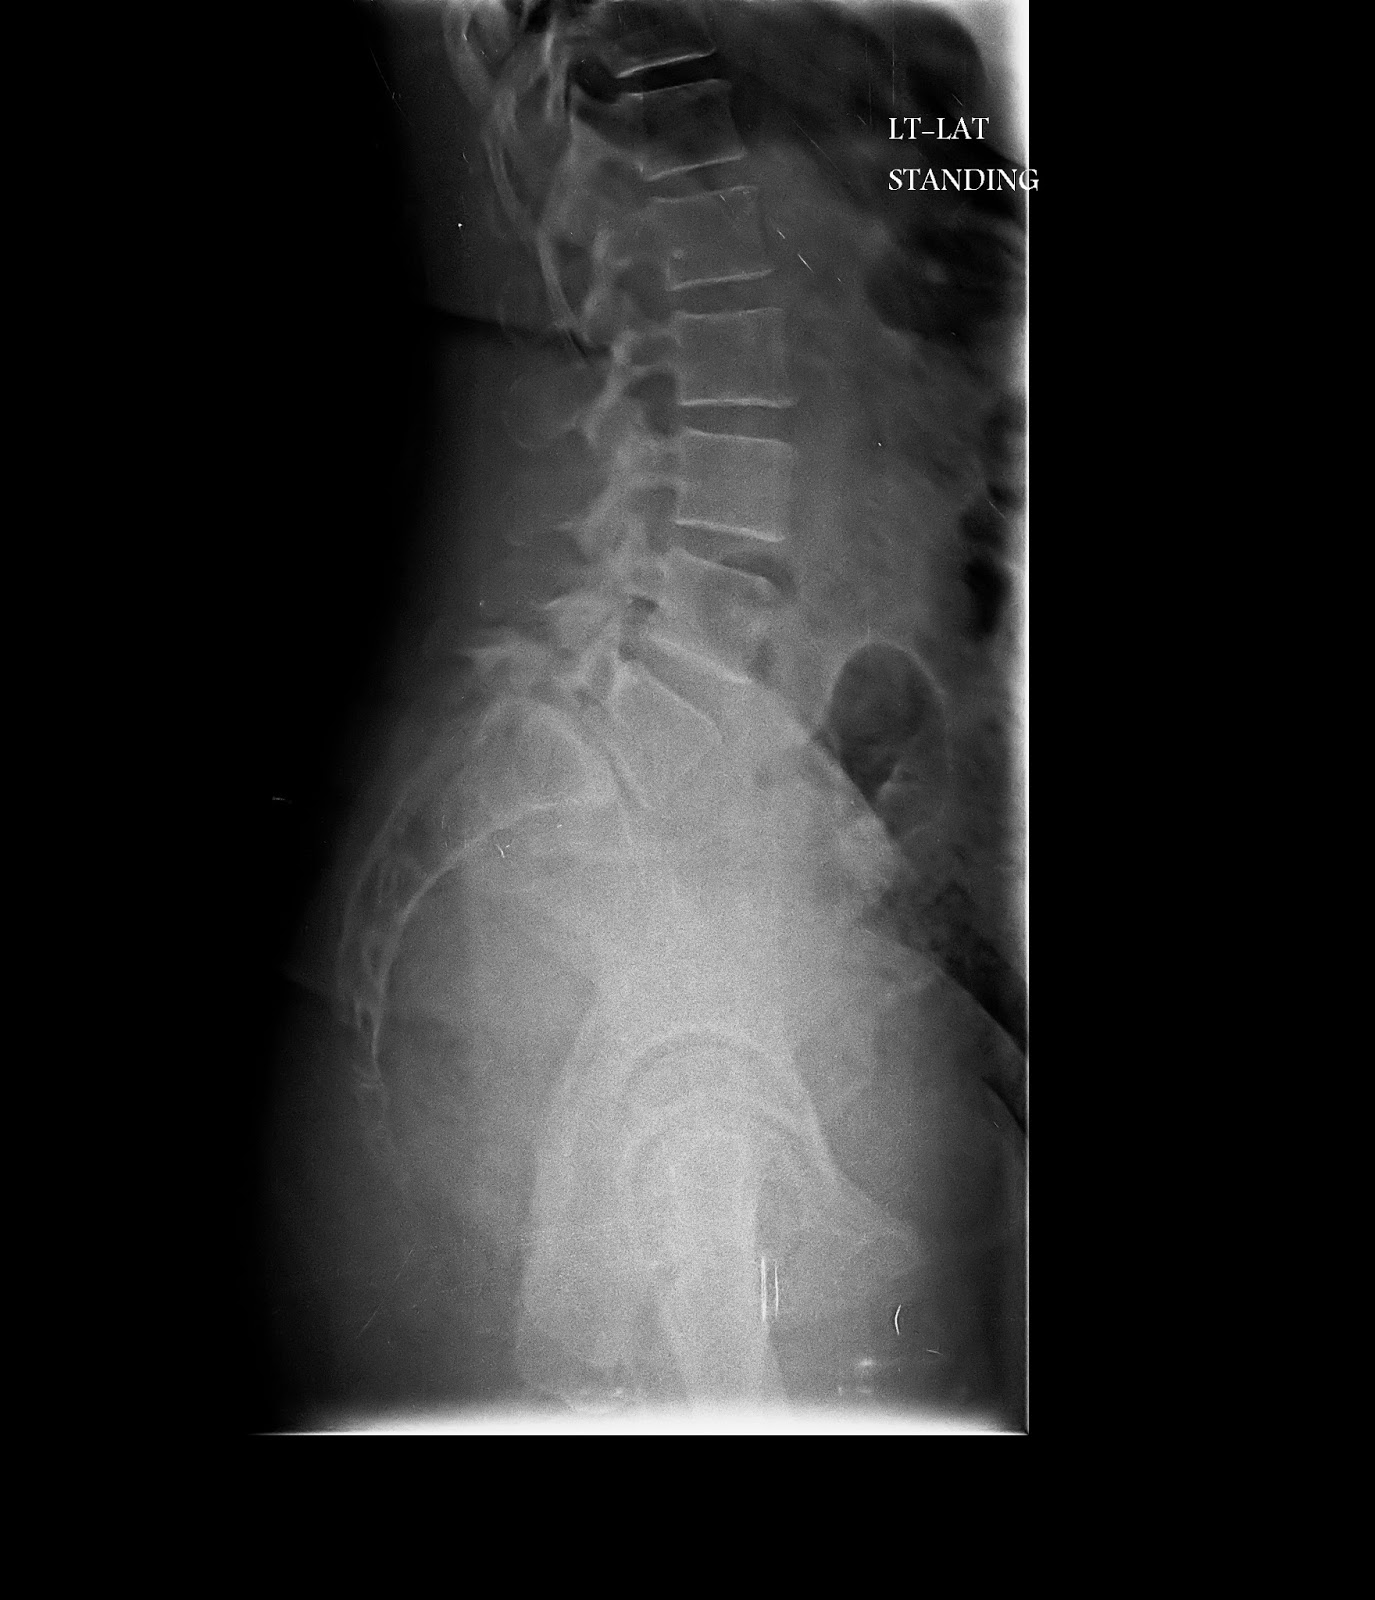

Implies the presence of bilateral spondylolysis and significant spondylolisthesis. Occurs with marked anterolisthesis of l5 on s1. Spondylolisthesis is the displacement of one spinal vertebra compared to another.